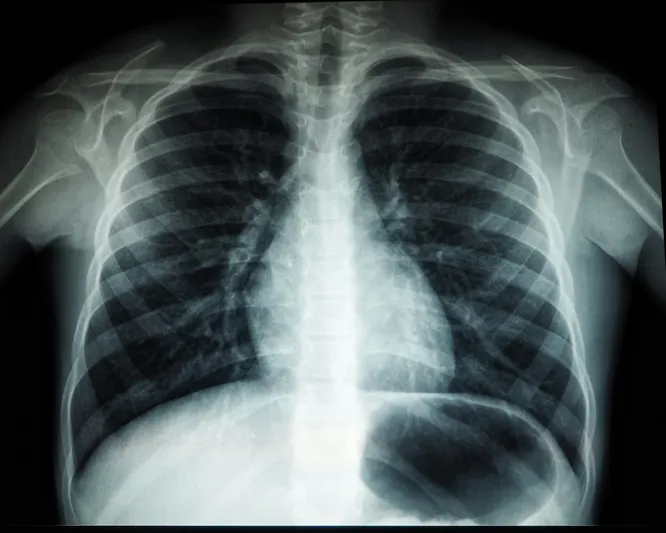

Туберкулез — инфекционное заболевание, которое можно предотвратить и вылечить. Его вызывают бактерии (палочка Коха), которые чаще всего поражают легкие. Он распространяется воздушно-капельным путем при кашле, чихании и сплевывании мокроты. К основным опасностям туберкулеза относятся следующие факторы: